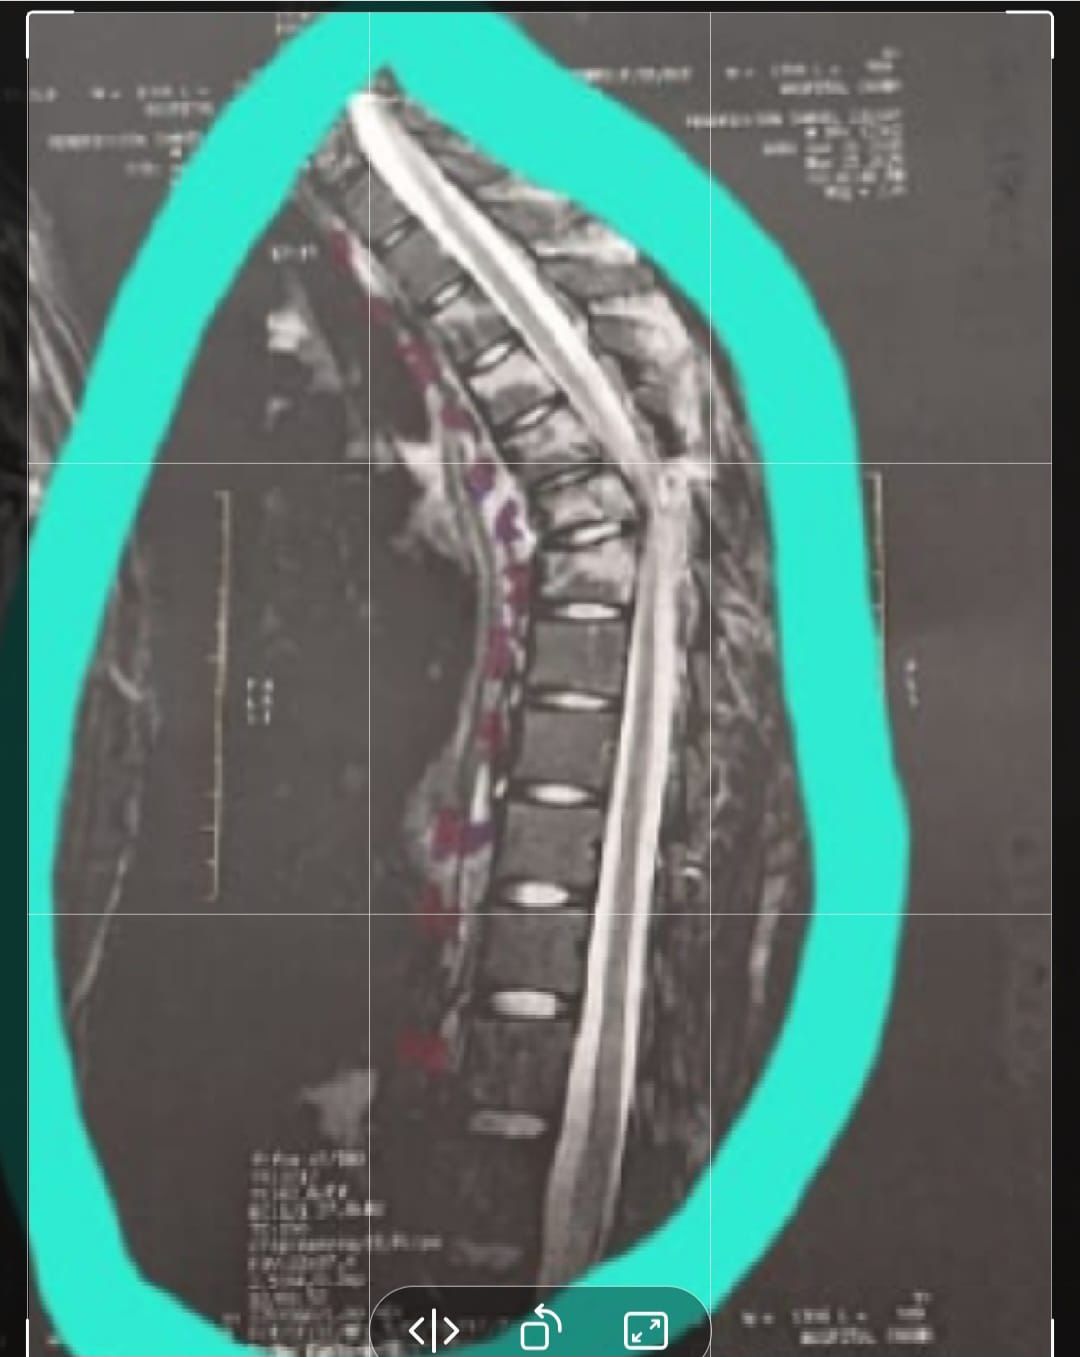

Rendrickson Samuel, de 19 anos, está internado no Hospital de Emergência do Agreste à espera de cirurgia na coluna após grave acidente - Foto: Acervo pessoal

Com o impacto, o jovem sofreu lesões graves na coluna, atingindo a região torácica. Desde então, permanece hospitalizado, imobilizado em uma cama, enfrentando dores constantes e o medo de perder os movimentos das pernas.